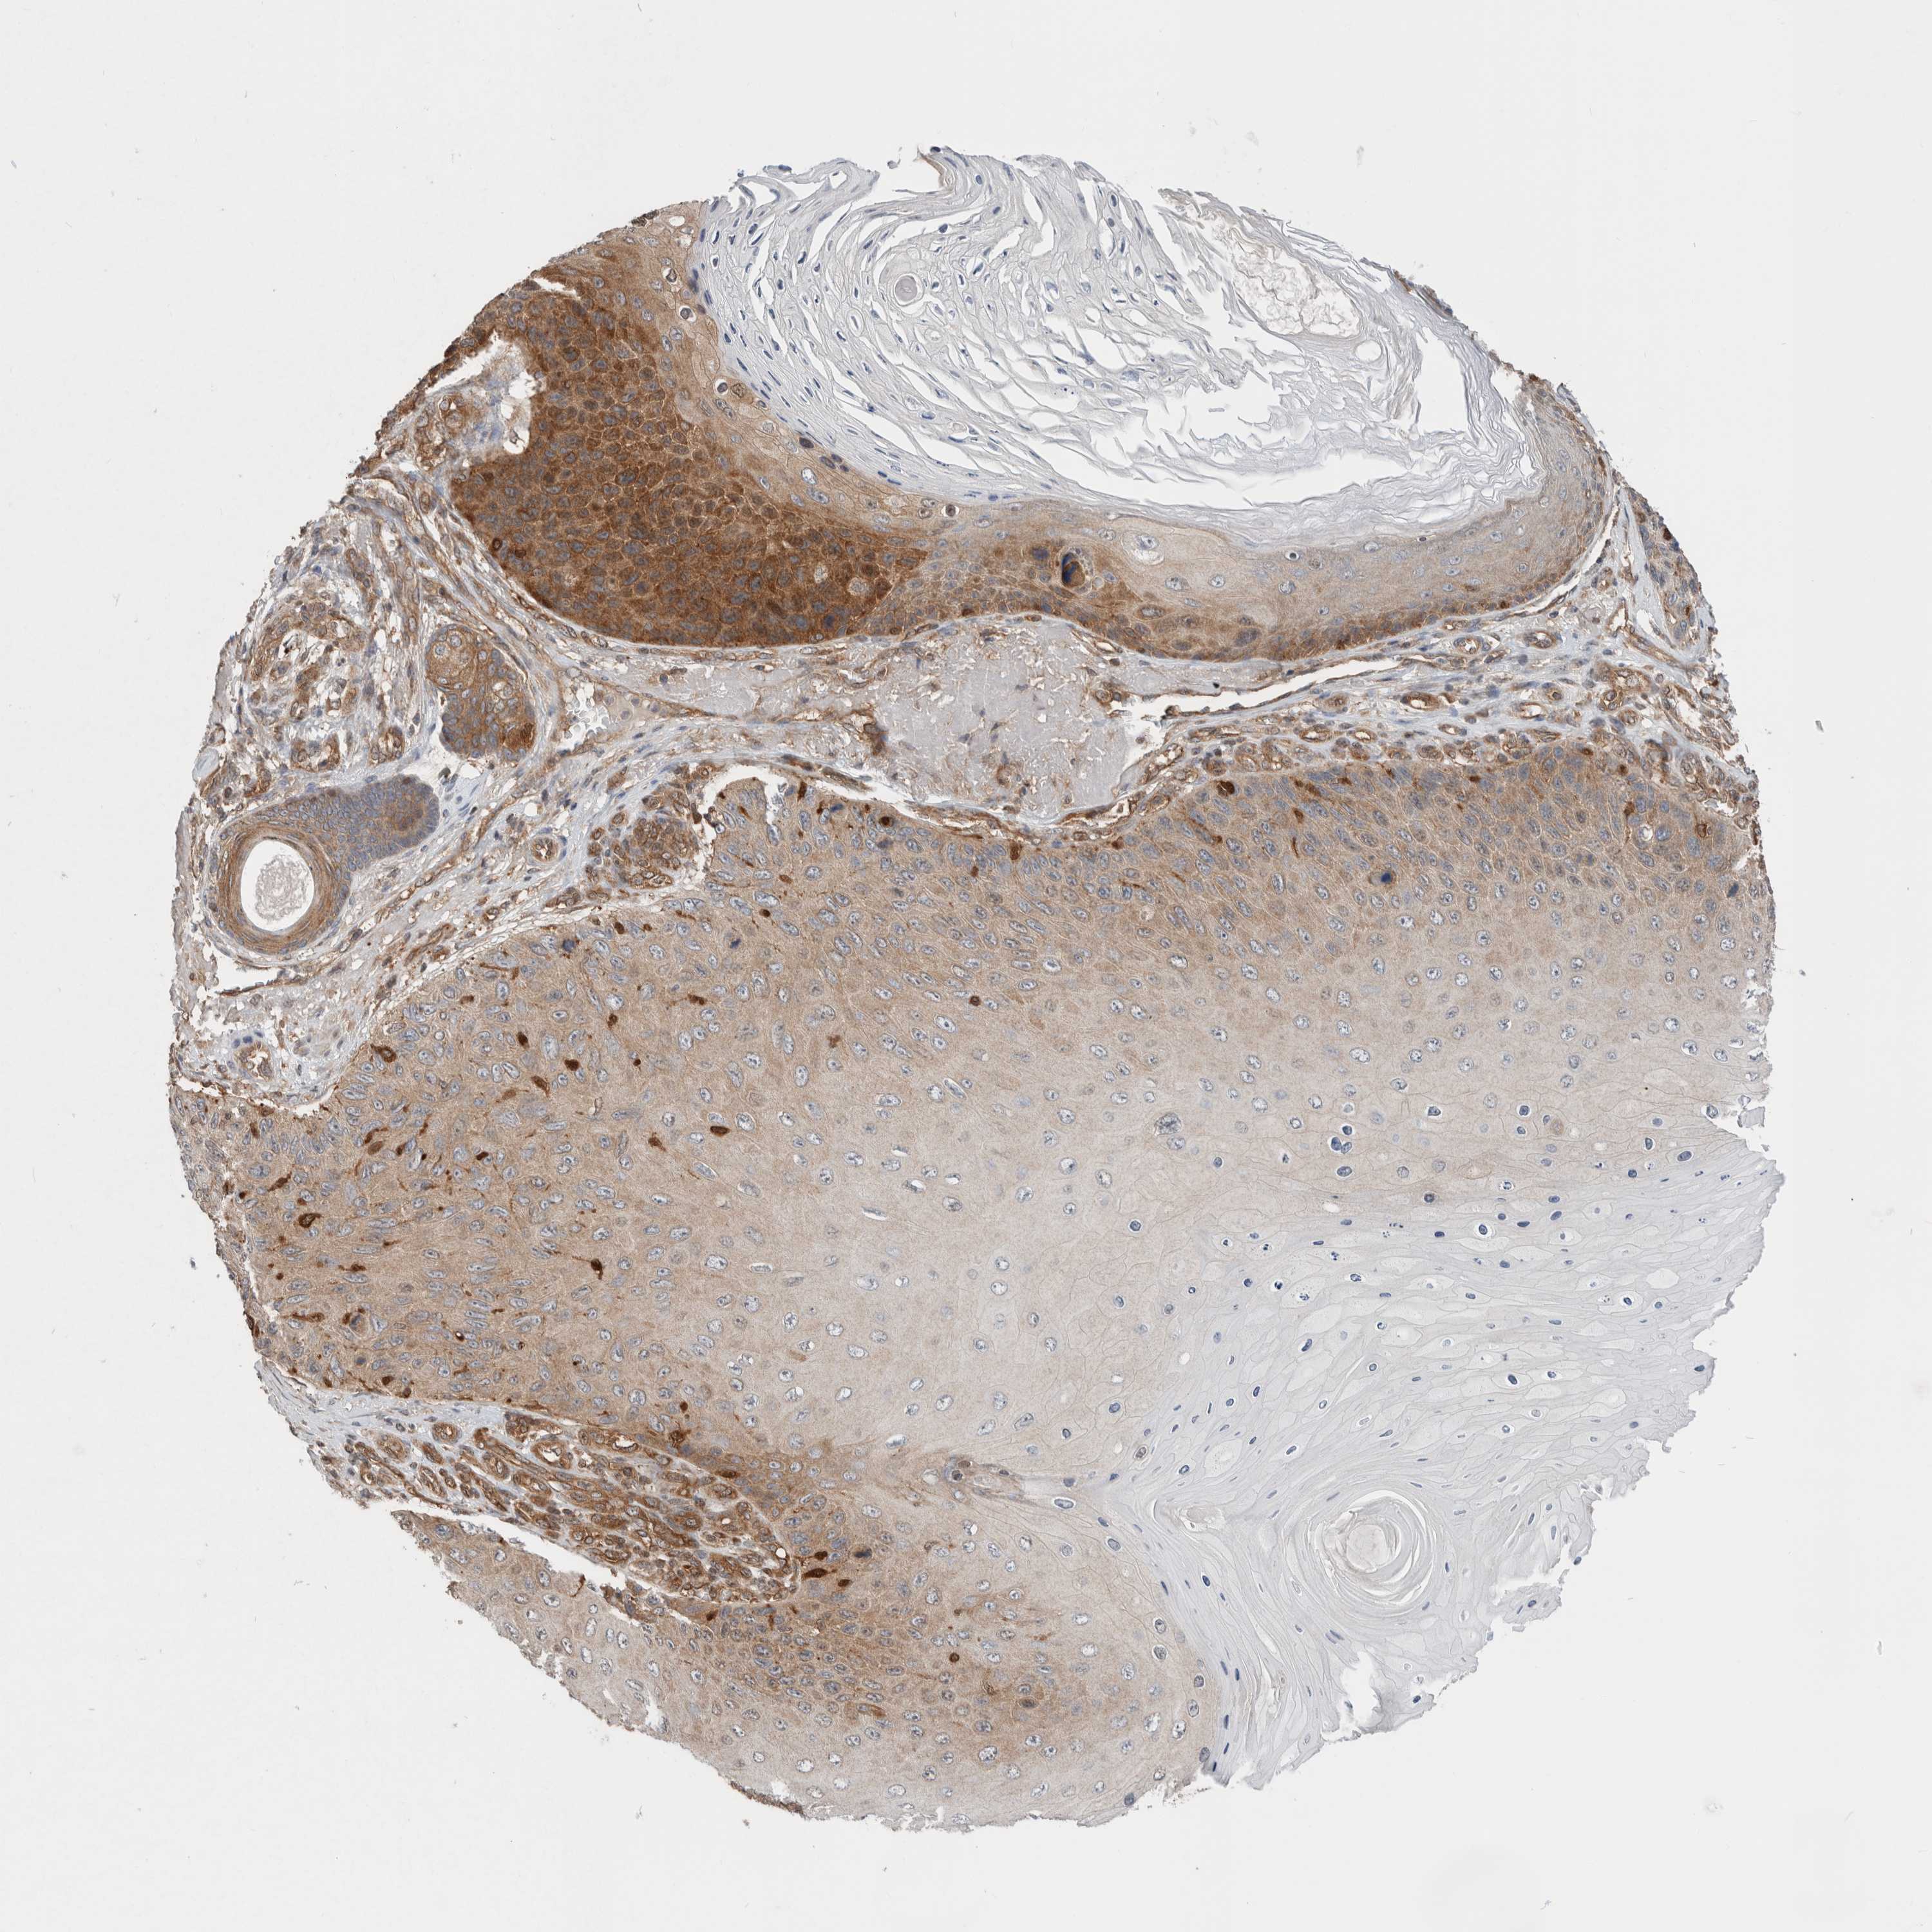

CANCER SKIN CANCER Show tissue menu

SKIN CANCER - Protein expressioni

A mouse-over function shows sample information and annotation data. Click on an image to view it in a full screen mode. Samples can be filtered based on level of antibody staining by selecting one or several of the following categories: high, medium, low and not detected. The assay and annotation is described here.

Antibody stainingi

Antibody staining in the annotated cell types in the current human tissue is reported as not detected, low, medium, or high, based on conventional immunohistochemistry profiling in selected tissues. This score is based on the combination of the staining intensity and fraction of stained cells.

Each image is clickable and will lead to virtual microscopy that enables deeper exploration of all samples and also displays staining intensity scores, fraction scores and subcellular localization as well as patient and tissue information for each sample.

HPA030419

HPA030420

HPA030422

CAB025196

CAB080286

CAB080287

Basal cell carcinoma

Squamous cell carcinoma, NOS

Squamous cell carcinoma, metastatic, NOS